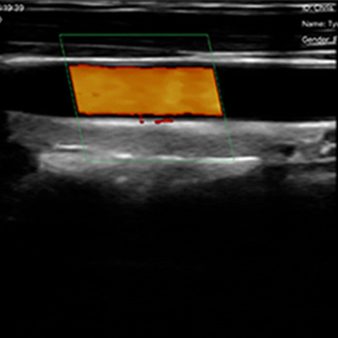

| Modo de escaneo | B, B/M, Color, PW |

Modos de escaneo

B, B/M, Color, PW

Longitud, área, velocidad, FC, desviación estándar, obstetricia, medición automática de vasos sanguíneos

Vascular